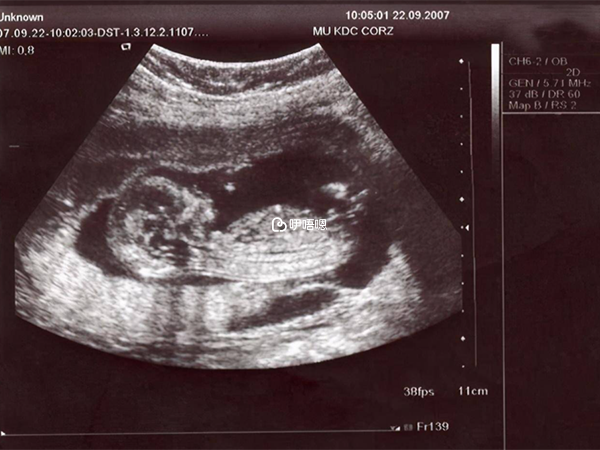

想开后觉得轻松了,很长一段时间我不再看帖。然后顺利满三个月去建档,唐筛的时候我是低风险,但是考虑到我老公是吃替诺的,我还是去做了无创dna,我觉得自己瞎担心不如花2000多买个安心,当然结果也都是好的。后面的检查都按医生要求去做,糖耐,大排畸都是一次过。

其中说一下大排畸,我是在公立医院做的,当时是提前一个多月预约的大排畸,我一直以为就是四维,结果是三维,后来了解到其实都是一样的,说明白点四维成像立体,可以给宝妈们看到宝宝就行一个噱头一样,三维对医生技术要求更高,一般大的公立医院没有四维的。